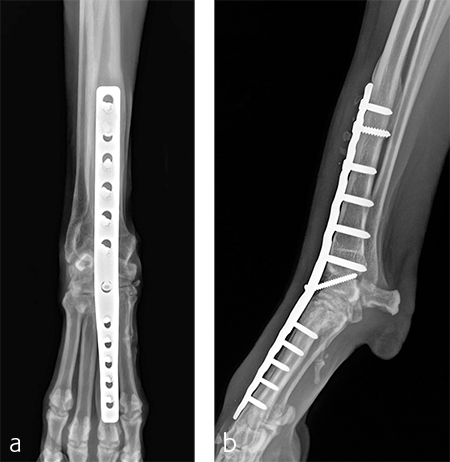

The patient was returned to normal activity 4 months after surgery. Radiographic examinations at 6 and 6.5 months after surgery revealed stable implants and fusion of the carpus (Fig 7 and 8). Functional outcome was excellent 1 year postoperatively. The patient had returned to full weight-bearing without lameness and the carpus was pain-free and stable.